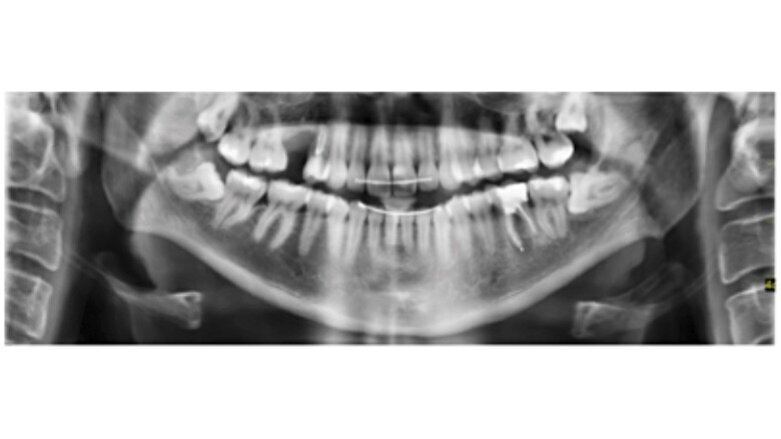

Fig. 1. OPG del paciente en dónde se puede observar una imagen radiolúcida compatible con una lesión apical en el diente 3.6.

Paciente de 27 años de edad que acude a la consulta para salvar un diente. En el examen clínico presenta dolor a la percusión.

Diagnosticamos una periodontitis apical sintomática con un tratamiento de conductos previo. Se decidió realizar la reendodoncia del diente 3.6. y proceder a su restauración definitiva.